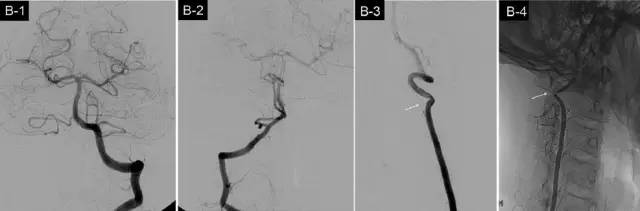

从影像学来看颈椎病为何会引起眩晕